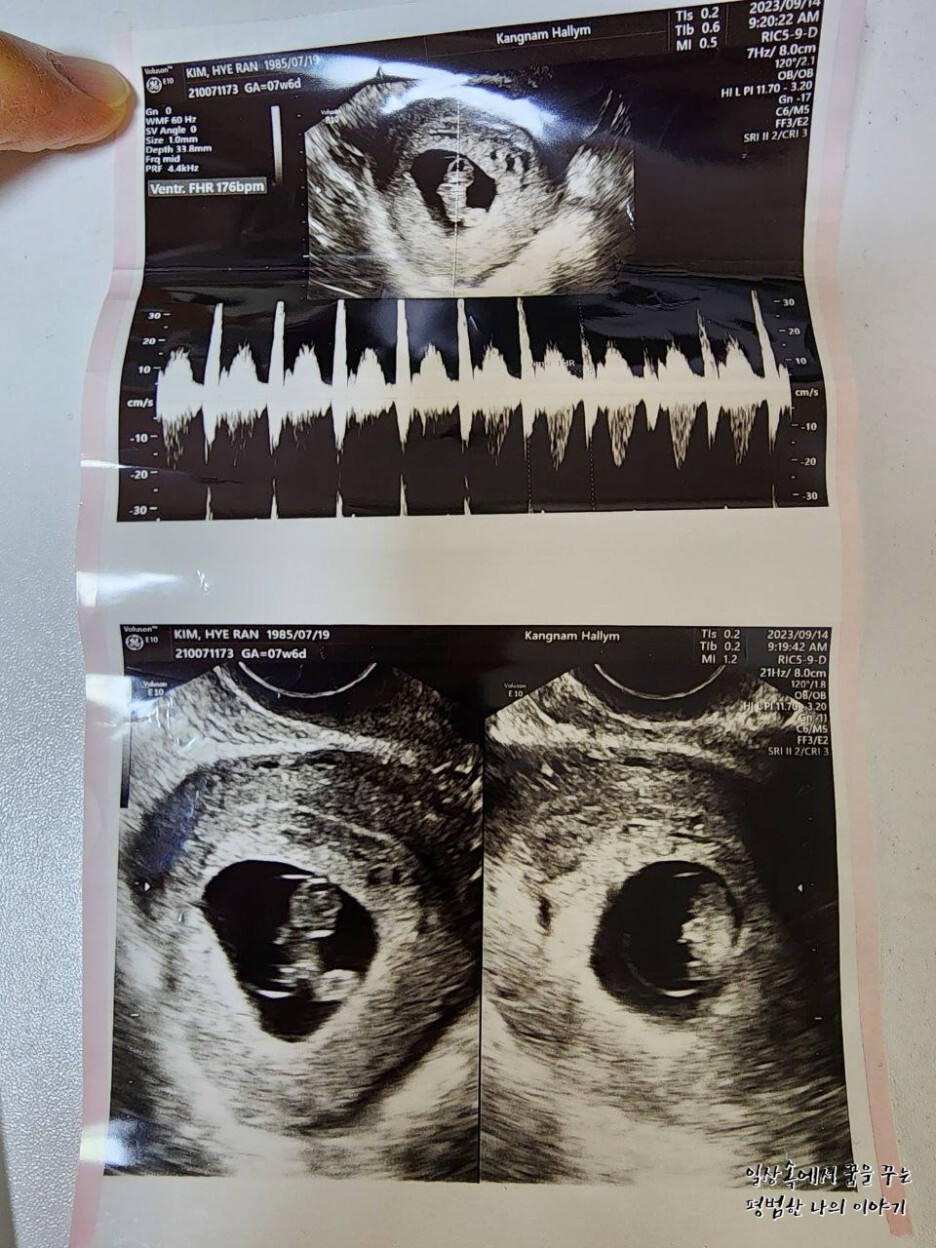

심장 박동 수는 5주~7주가 될수록 빨라지는데 그게 정상이라고 한다. 레오나는 심장박동 수가 7주 차 6일에 176bpm이므로 평균에 비해 조금 빠른 편이긴 하지만 의사 선생님이 이 정도는 정상으로 간주한다고 하더라.(대학병원이라 그런 건지 진짜 심각한 증상이 아니면 대부분 괜찮다고 하심, 워낙 심각한 경우를 많이 봐서 그러실 듯) 그리고 평균적으로 16주가 지나면서부터는 태아의 심장박동 수가 느려지기 시작한다.